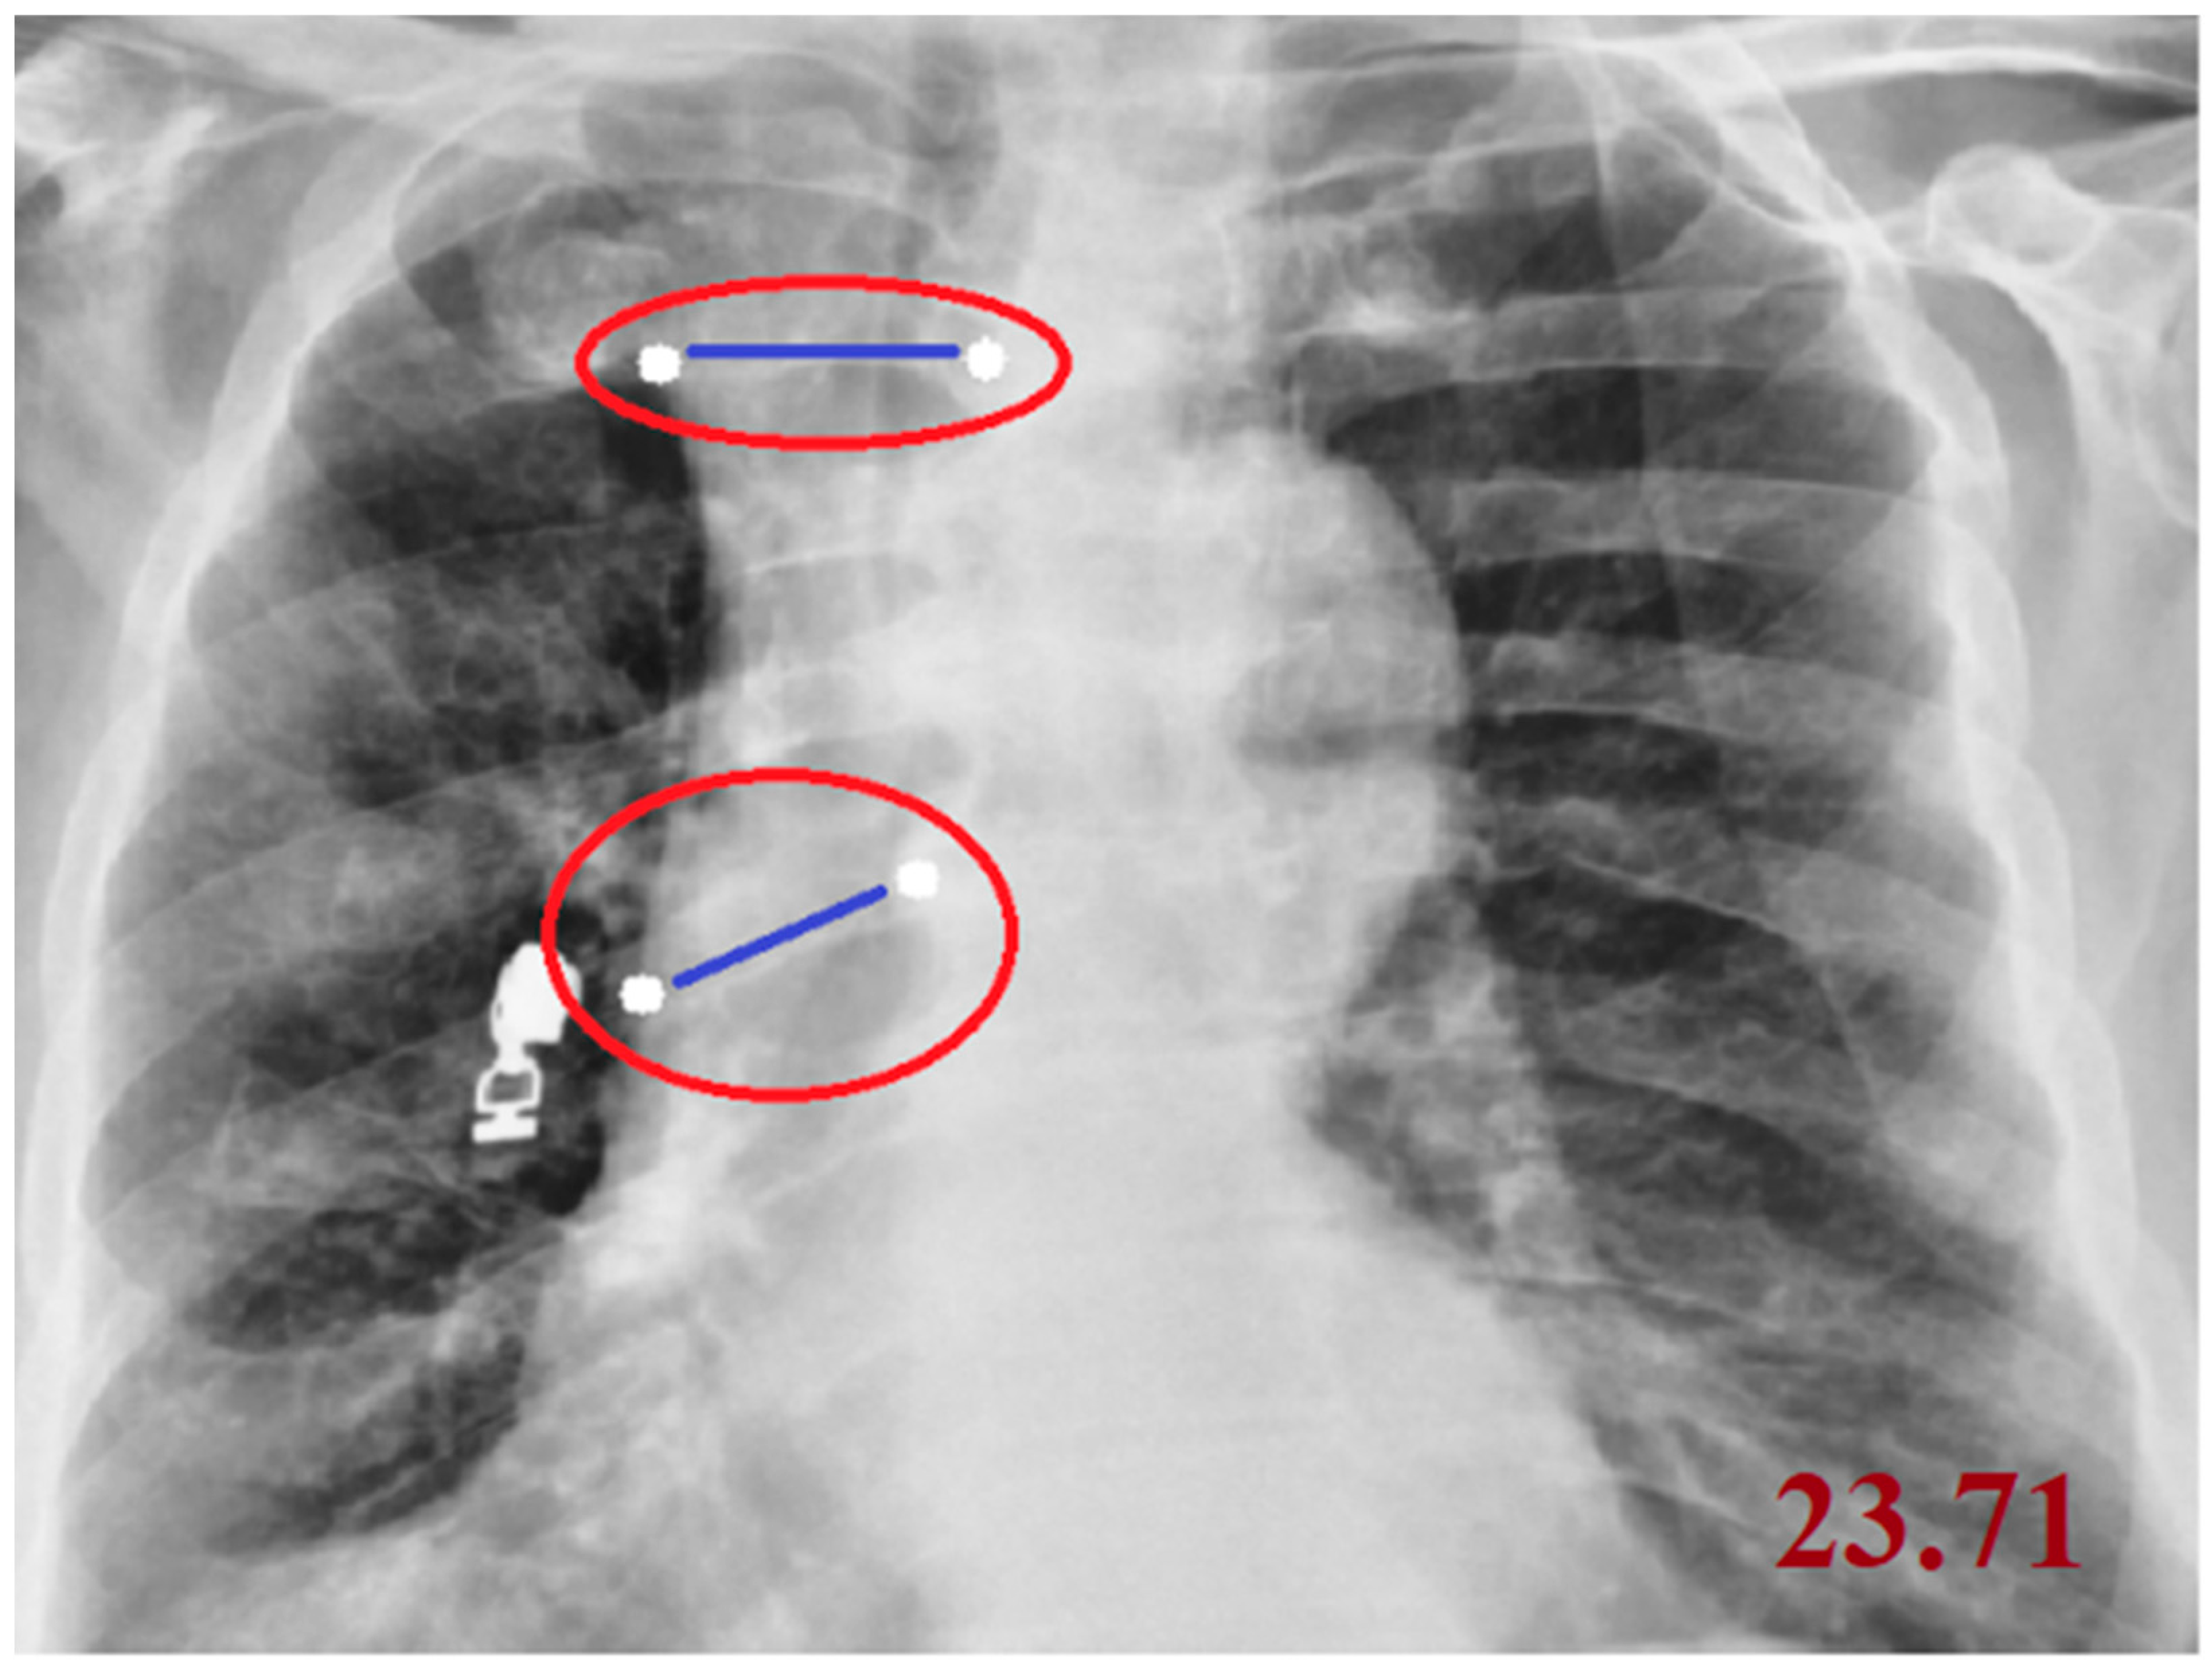

| CTR (Cardiothoracic Ratio) | cv2, numpy, tkinter | Calculates the ratio of cardiac width to thoracic width | Involves point selection and distance measurement |

| Cobb Angle | cv2, numpy, math, tkinter | Measures vertebral tilt and spinal curvature angle | Calculated using four manually selected points |